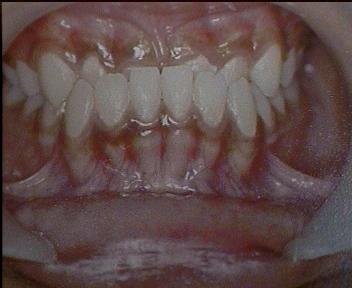

Class III Malocclusion

Malocclusion [Non Surgical correction]

Before Treatment Intra Oral

After Treatment Intra Oral